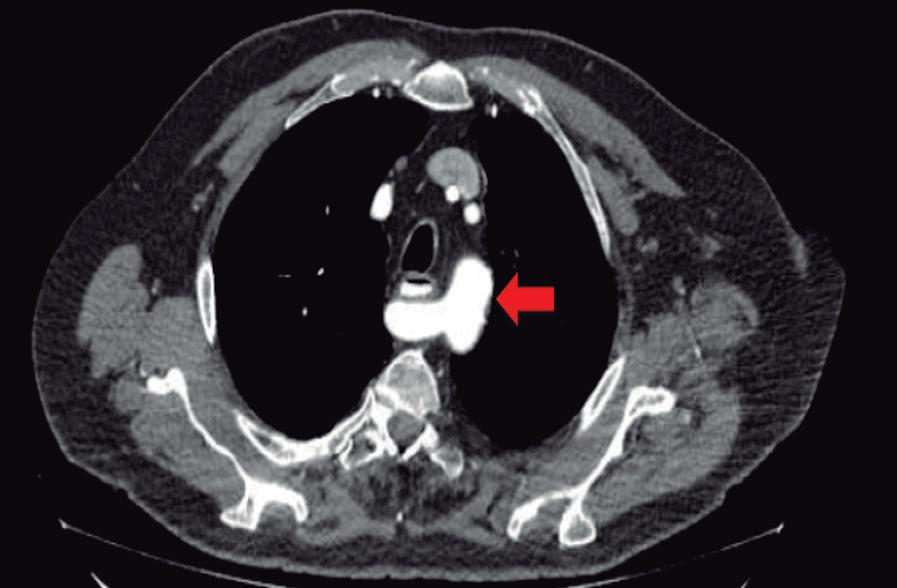

Paciente con vómitos en el periodo posoperatorio

Germán Francisco Rojas, Gabriel Adrián Mariño Camacho, Jesica Antonella Andruetto, Martín José Drago, Alejandro Moreira Grecco, Mariano Volpacchio, Esteban González Ballerga